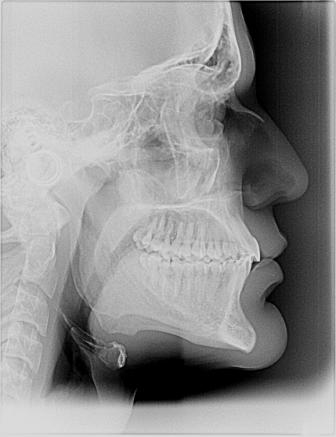

Nel nostro Studio impieghiamo un sistema radiografico computerizzato, il Vista Scan Plus della Dürr che consente di ottenere immagini di alta qualità (vedi confronto analogico/digitale) con dosi radiogene sensibilmente più basse per il paziente.

Con Vistascan Plus siamo in grado di ottenere, nel giro di pochi minuti, tutte le immagini che ci servono per un corretto ausilio diagnostico: bitewing, endorali, ortopantomografie, teleradiografie.